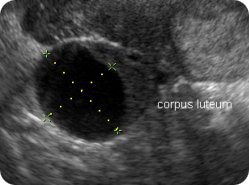

Ултразвук

Ултразвучниот преглед во 6. недела опфаќа приказ на матката, мерење на должината на ембрионот (CRL) и мерење на жолчната кеса (Yolk sac). На сликите е прикажано и жолтото тело кое настанува од прснатиот фоликул во јајникот и кое има хормонска улога во одржување на бременоста. Должината на ембрионот (CRL) во овој период изнесува околу 5,5 mm.